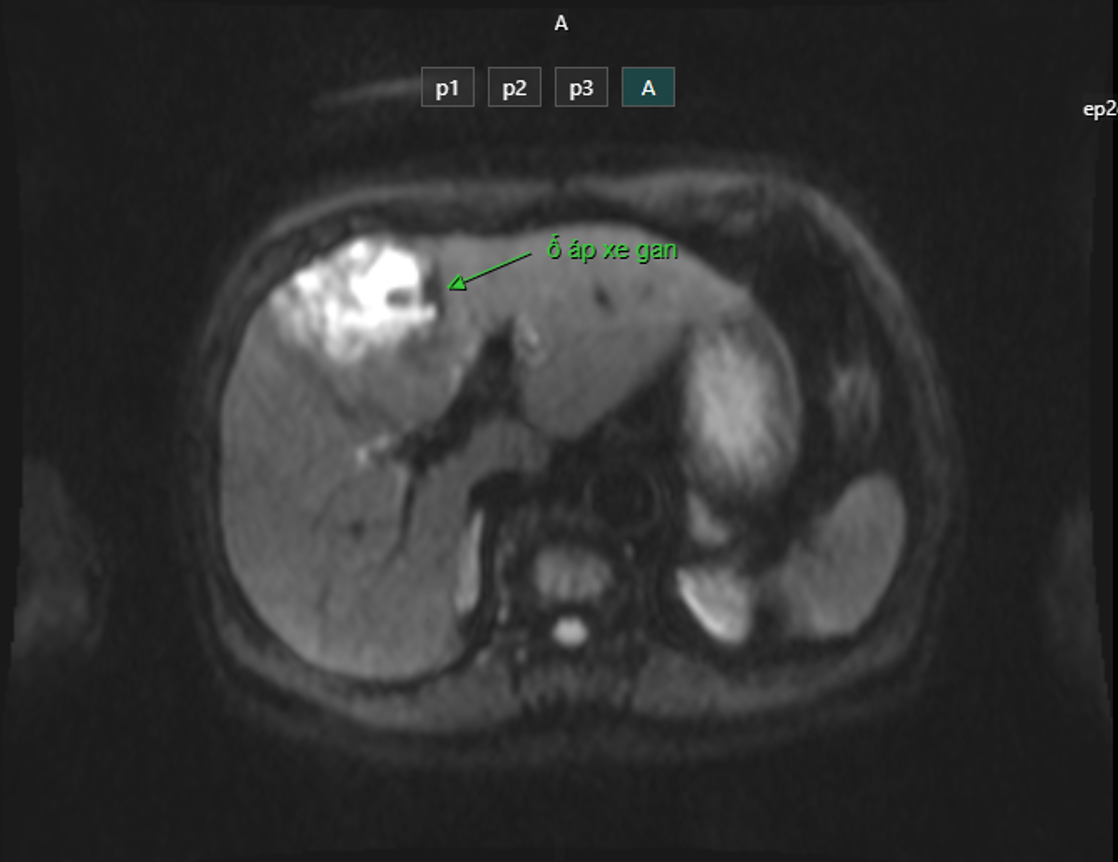

Hình ảnh ổ áp xe gan phân thuỳ IV trên phim chụp cộng hưởng từ

Mới đây khoa Cấp cứu Bệnh viện Giao thông vận tải tiếp nhận bệnh nhân nam 88 tuổi có tiền sử tăng huyết áp, đái tháo đường nhập viện trong tình trạng sốt cao liên tục ngày thứ 1, đau bụng mạn sườn phải, xét nghiệm tình trạng nhiễm khuẩn nặng (Bạch cầu: 21 G/L, procalcitonin: 37), tiểu cầu giảm (78 G/L), có rối loạn đông máu (chỉ số INR: 1.44), siêu âm bụng gan mật có khối không đồng nhất phân thùy IV, theo dõi khối áp xe gan. Ngay lập tức bệnh nhân được cấy máu, phối hợp kháng sinh truyền tĩnh mạch, chụp cộng hưởng từ ổ bụng. Kết quả chụp cộng hưởng từ là ổ áp xe gan phải hạ phân thuỳ IV kích thước 55 x 44 mm.